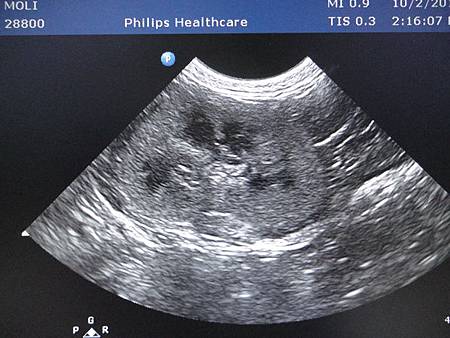

掃超音波

儀器的聲音和醫生的解說...

結果令人傷心...

右腎的密度高,膽囊壁密度也高

但是形狀還可以,沒有膽泥淤積,肝臟的密度也還好

翻譯就是,腎臟的樣子不漂亮,還可以接受,膽囊要小心以後出問題

令人最煩惱的是左腎...

醫生很擔心的說,它已經萎縮了...

照片中可以看出來他的大小比右邊的小,雖說6月份才做過血檢

還有掃了膀胱,膀胱是正常的,沒有結石與結晶